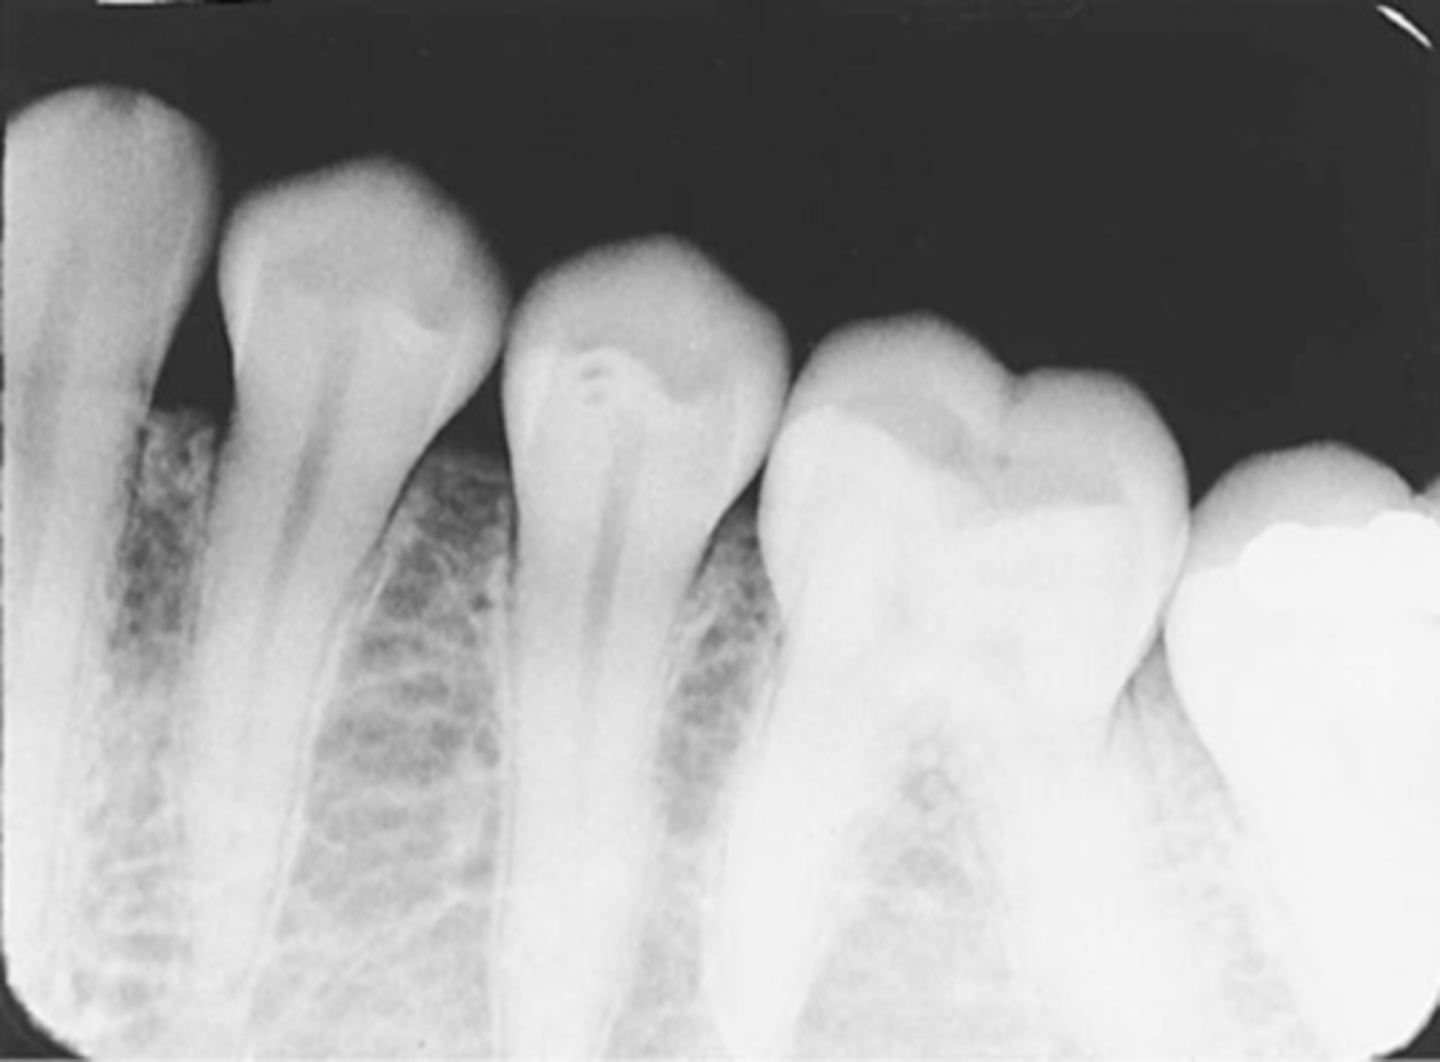

Incorrect Vertical Angulation-->Foreshortened Images

-Teeth appear short with blunted roots

-Vertical angulation was excessive, or too steep, resulting in images that are shorter than the actual teeth

-This occurs more often with the bisecting technique

-To prevent do not use excessive vertical angulation

Tube Head & PID-->Foreshortening of the image

-Excessive angulation (too steep) causing shortening of the anatomy of the teeth and/or cutting off occlusal or incisal edge.

Foreshortened image; Vertical angulation is too steep, Possible deflected film.